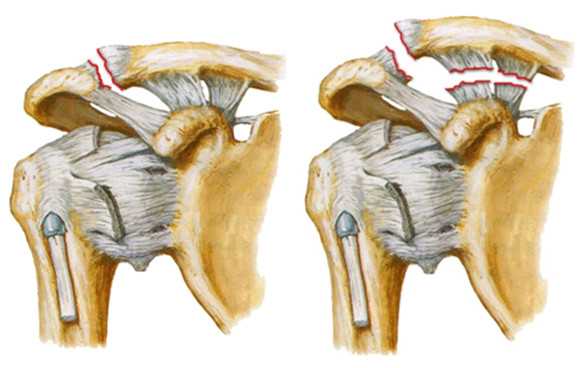

Один из вариантов оперативного лечения вывиха акромиального конца ключицы — синтез крючкообразной пластиной. Данная фиксация очень надежна, но имеет определенные недостатки.

- Во-первых, для данной операции требуется большой разрез (7-10 сантиметров).

- Во-вторых, при установке пластины, крючок заводят под акромиальный отросток, располагая рядом с вращательной манжеткой. В дальнейшем, при движении плечом, сухожилия травмируются о пластину, вызывая дискомфорт, болевые ощущения, ограничение движения. В результате это может привести к повреждению сухожилий вращательной манжетки (сухожилия надостной мышцы).

- В-третьих, известны случаи, когда происходил перелом ключицы по внутреннему краю пластины.

В связи с этим пластину рекомендуется удалять через 4-6 месяцев. А это повторная операция.

Еще один вариант операций - синтез крючкообразной пластиной

Такая фиксация очень надежна, но и она не лишена недостатков.

Фиксация ключицы крючкообразной пластиной (hook plate)